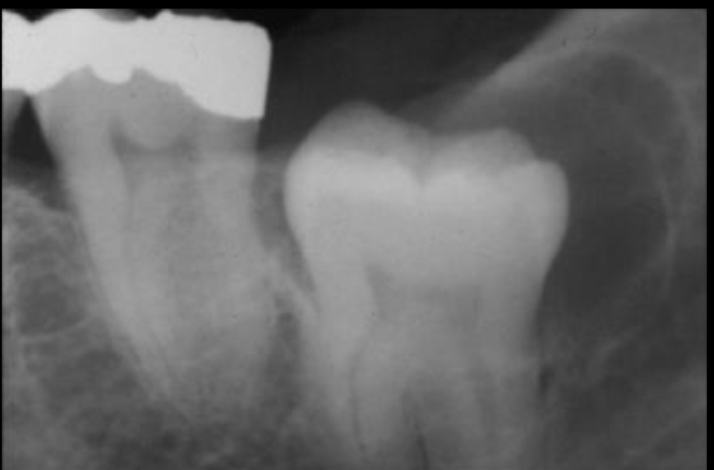

10

A

expansion of dentigerous cyst